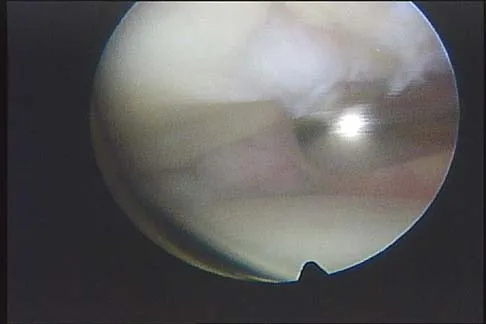

A 21-year-old soccer player reports pain and is unable to straighten his knee following an acute injury during a game. He is unable to continue to play. An MRI scan is shown in Figure 3. What is the next most appropriate step in management?

Explanation